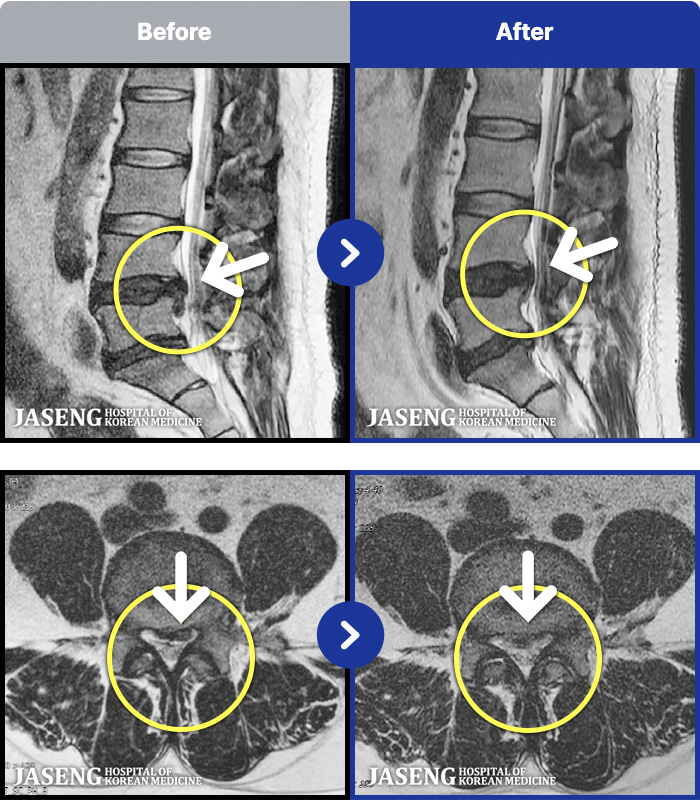

MRI ġ

1,299 MRI ũ ʸ Ȯϼ.